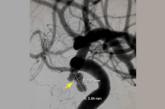

Cerebral angiography showing a posterior communicating artery aneurysm